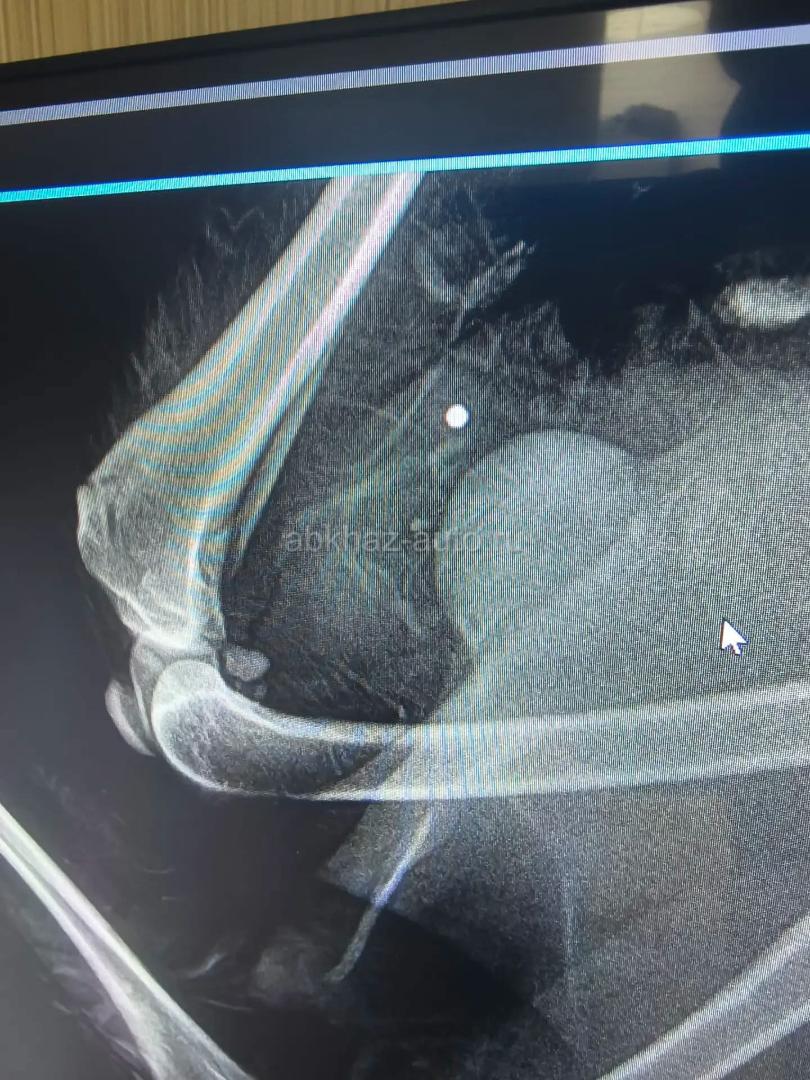

Помощь собаке 🙏

Дополнительная информация: https://chat.whatsapp.com/CPJrkdCqUGg8WK3iQZBeYd?mode=gi_t Вступайте в группу помощи Антошке из Абхазии. Ему предстоит операция,без которой Антошка будет инвалидом. Нам предстоит операция на позвоночнике и удаление пуль из тела. Сбор только на операцию - почти 80000 руб.. Просим помощи для Антошки...❤️🙏❤️🙏❤️🙏❤️ Карта помощи : 5536914116400338 - Тинькофф Кирса Ребекка Сергеевна PayPal: tomborn63@online.de ЛЮБАЯ СУММА , ДАЖЕ 100₽ ♥️ ЗАХОДИТЕ В ГРУППУ, ТАМ ВСЕ ОБ АНТОШКЕ